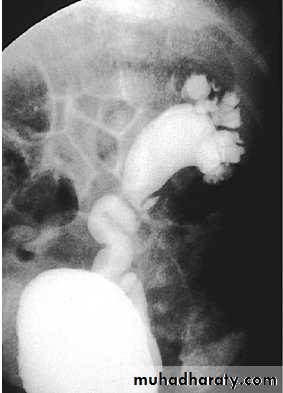

What's Diagnosis?

• UPJ obst. Ureteric stricture and dilation of renal pelivsCan you grade this Reflux?

Grade 5

-Obliteration of papillary impressions(fornices)-Dilated and torturous ureter